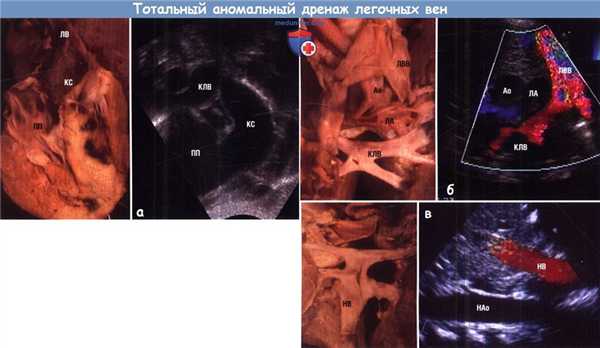

(А) Тотальный аномальный дренаж легочных вен в коронарный синус из субкостальной позиции.

Обратите внимание на расширенный коронарный синус (КС) на обоих изображениях. На ЭхоКГ также отражен венозный коллектор легочных вен, соединяющийся с коронарным синусом.

(Б) Тотальный аномальный дренаж легочных вен в левую вертикальную вену из супрастернальной позиции.

Обратите внимание, что направление кровотока в вертикальной вене отличается от направления кровотока в левой ВПВ.

(В) Тотальный аномальный дренаж легочных вен ниже уровня диафрагмы.

На анатомическом препарате видна область слияния легочных вен, тогда как на ЭхоКГ продемонстрированы нисходящие вены в месте впадения на уровне печени.

Обратите внимание, что кровоток всегда направлен от сердца.

Ао — аорта; КЛВ — коллектор легочных вен; ЛА—легочная артерия; ЛВ—легочная вена; ЛВВ—левая вертикальная вена; НАо—нисходящая аорта; НВ — нисходящая вена; ПП — правое предсердие.